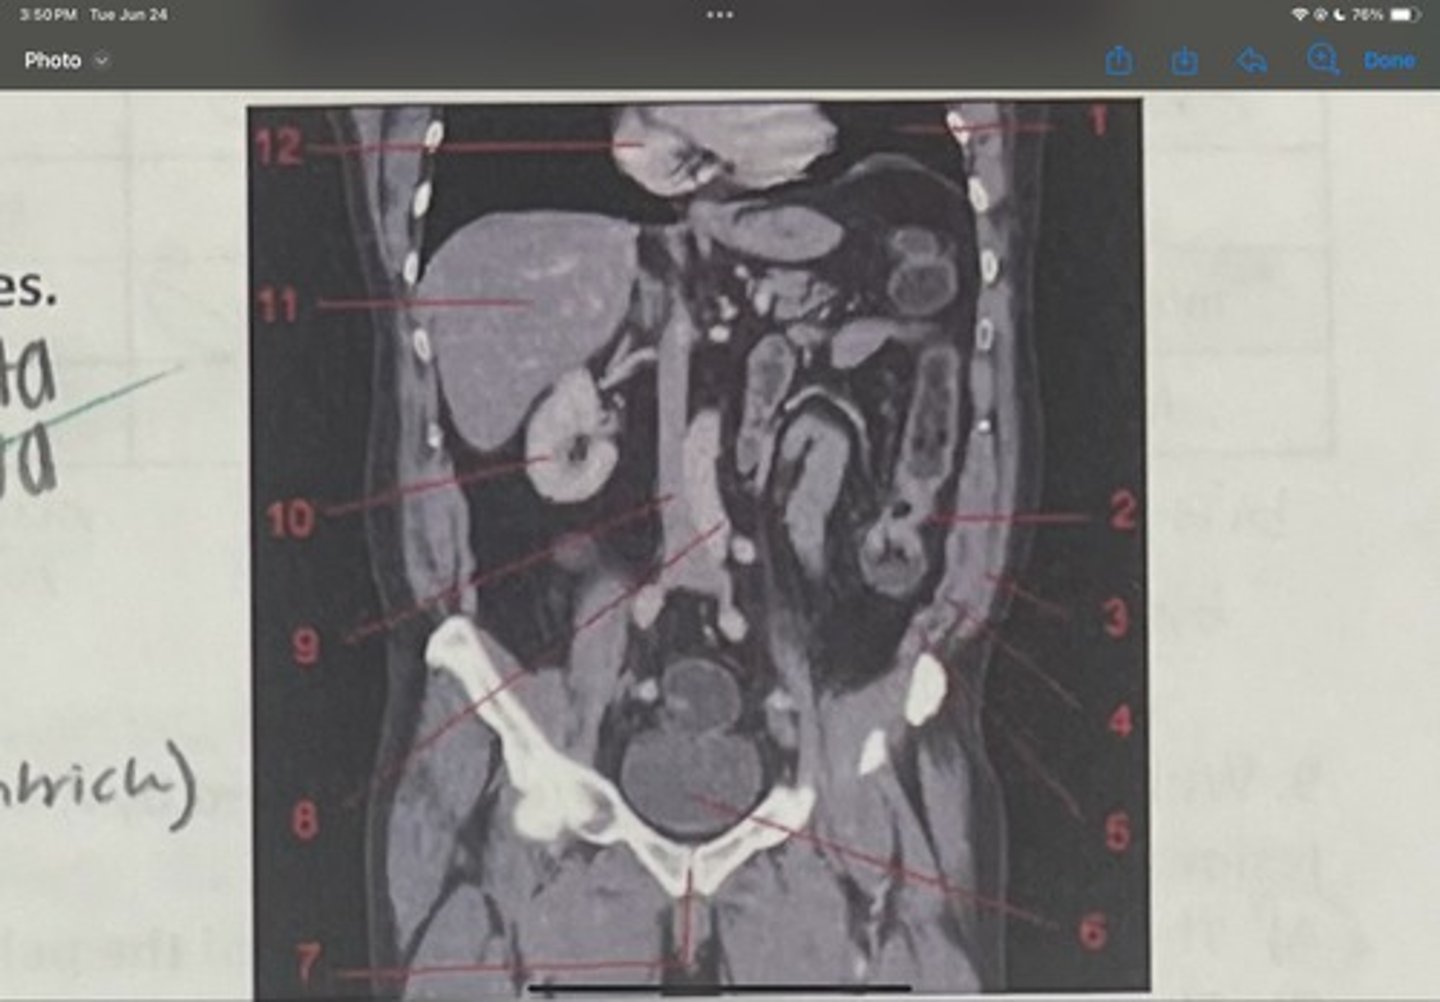

What is 1

Descending colon

What is 2

External oblique

What is 3

Internal obliques

What is 4

Transversus abdominis

What is 5

Bladder

What is 6

Pubic sysmphysis

What is 7

Abdominal aorta

What is 8

Inferior vena cava

What is 9

Right kidney

What is 10

Liver

What is 11

Heart (right ventricle)

What is 12

Subcostal nerve (T12)

What is 1

Illiohypogastric nerve (T12/L1)

What is 2

Illioinguinal nerve (L1)

What is 3

Genitofemoral nerve (L1-L2) ; on top of psoas

What is 4

lateral femoral cutaneous nerve (L2-L3)

What is 5

Femoral Nerve (L2-L4)

What is 6

Obturator nerve (L2-L4)

What is 7

Renal artery

What is the 1st one

Abdominal aorta

What is the 2nd one

Common iliac artery

What is the 3rd one

External iliac artery

What is the 4th one

Internal iliac artery

What is the 5th one

right common iliac artery blockage

What is the pathology of the image